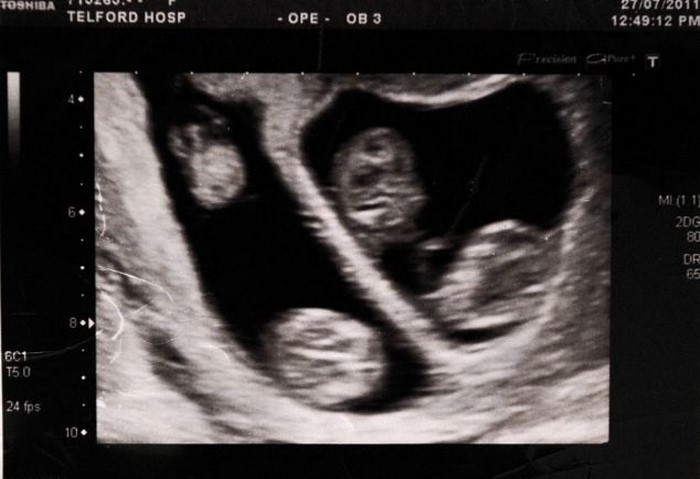

Cuando el médico diagnosticó que Charlene estaba embarazada, ella y su pareja, Mark, estaban en el séptimo cielo de felicidad. Más tarde, se supo que la pareja tendría dos hijos, a la vez. Solo entonces, en una de las sesiones de ultrasonido, se descubrió qué, en el vientre de la futura madre, se gestaban cuatro pequeñas hermanas, a la espera de su nacimiento.

Después de consultar, la joven pareja rechazó la oferta de especialistas. Charlene y Mark decidieron arriesgarse, y darles a todas sus hijas la misma oportunidad de vivir. Ya en la semana 24 de embarazo, la madre tuvo que ser hospitalizada. ¡Seis semanas más tarde, cuatro hermosas niñas vinieron con éxito al mundo!